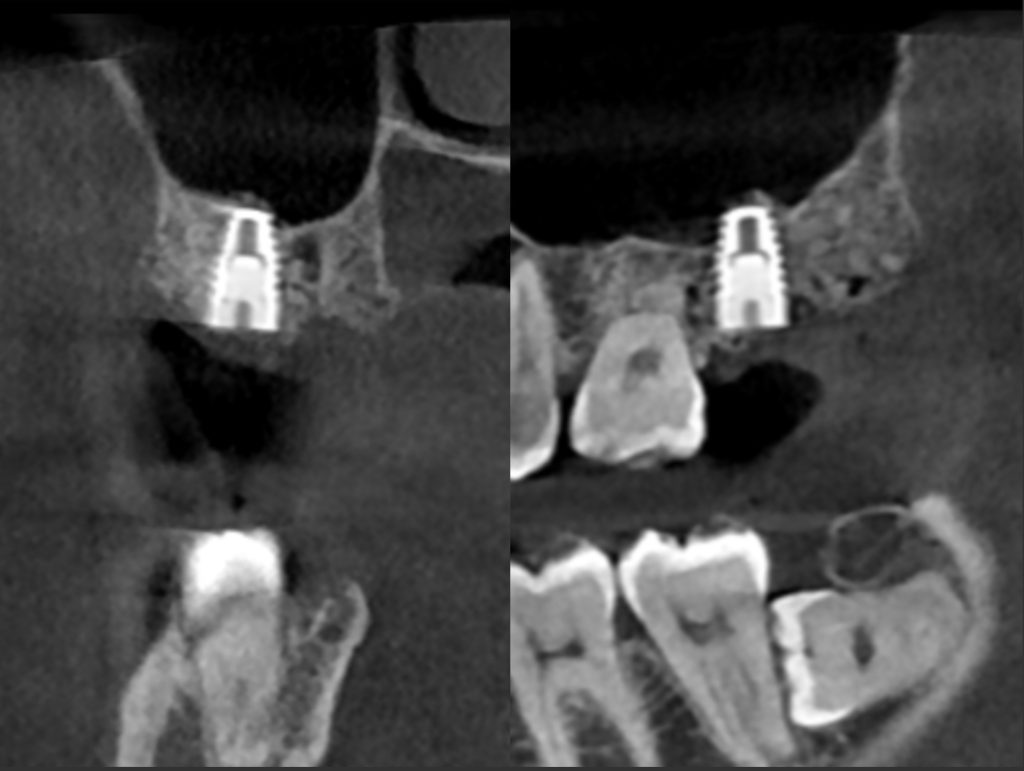

下記の症例は新しくローンチされるインプラントを前もって使用感を確認する為に、適したケースに使わせていただいております。

今回のケースは新しいインプラントを使うことで、骨造成の負担を減らし、清掃性を高める事ができました。